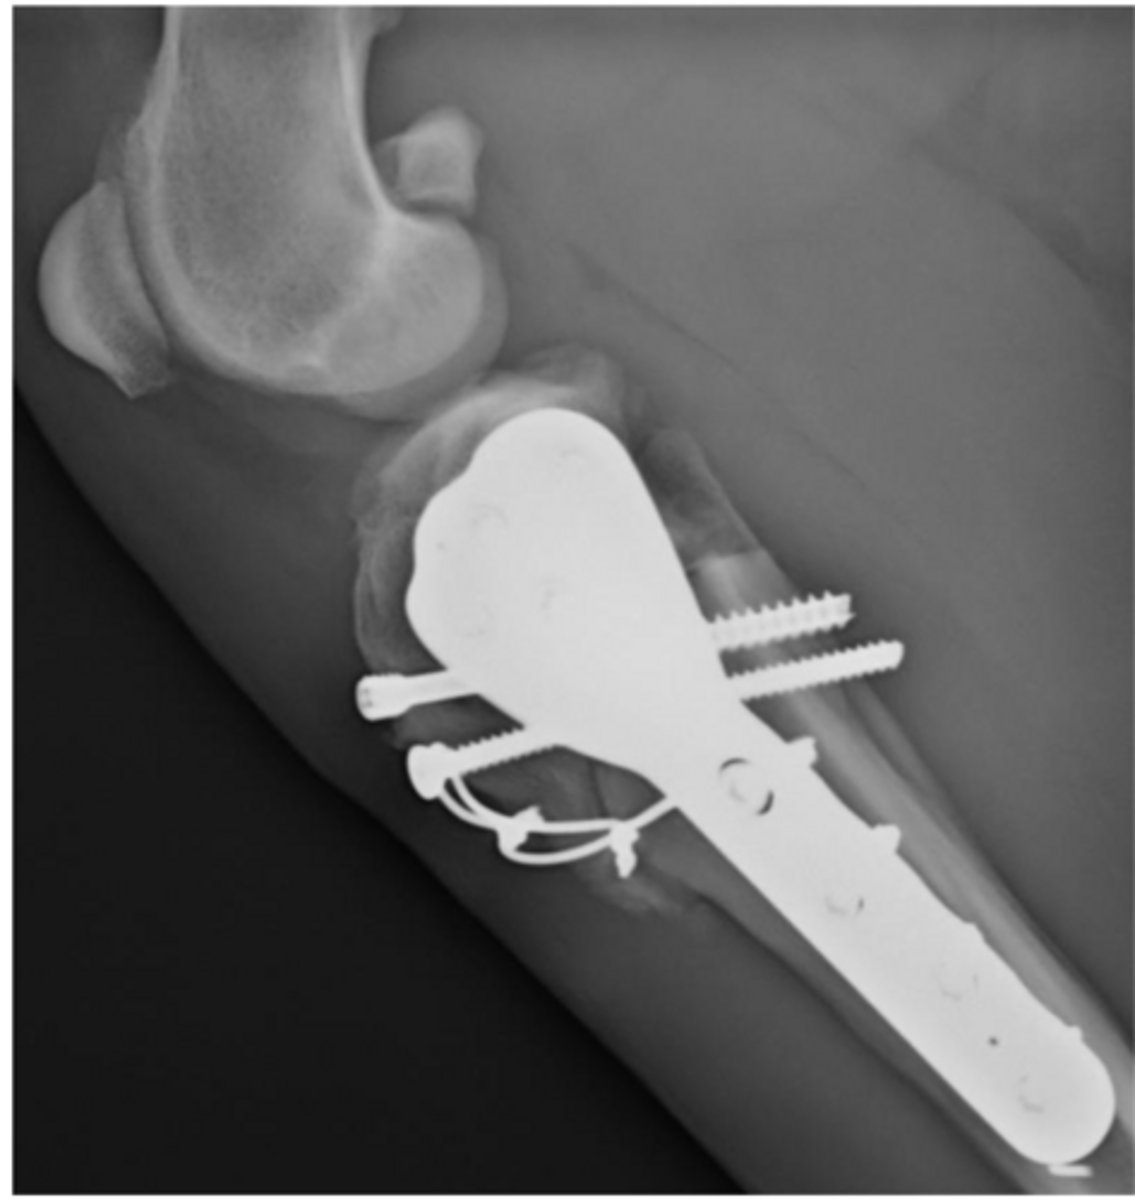

post-op RADS of TTA

what is shown here

CORA (CBLO) center rotation and angulation of tibia to correct angular limb deformity

what procedure is shown here